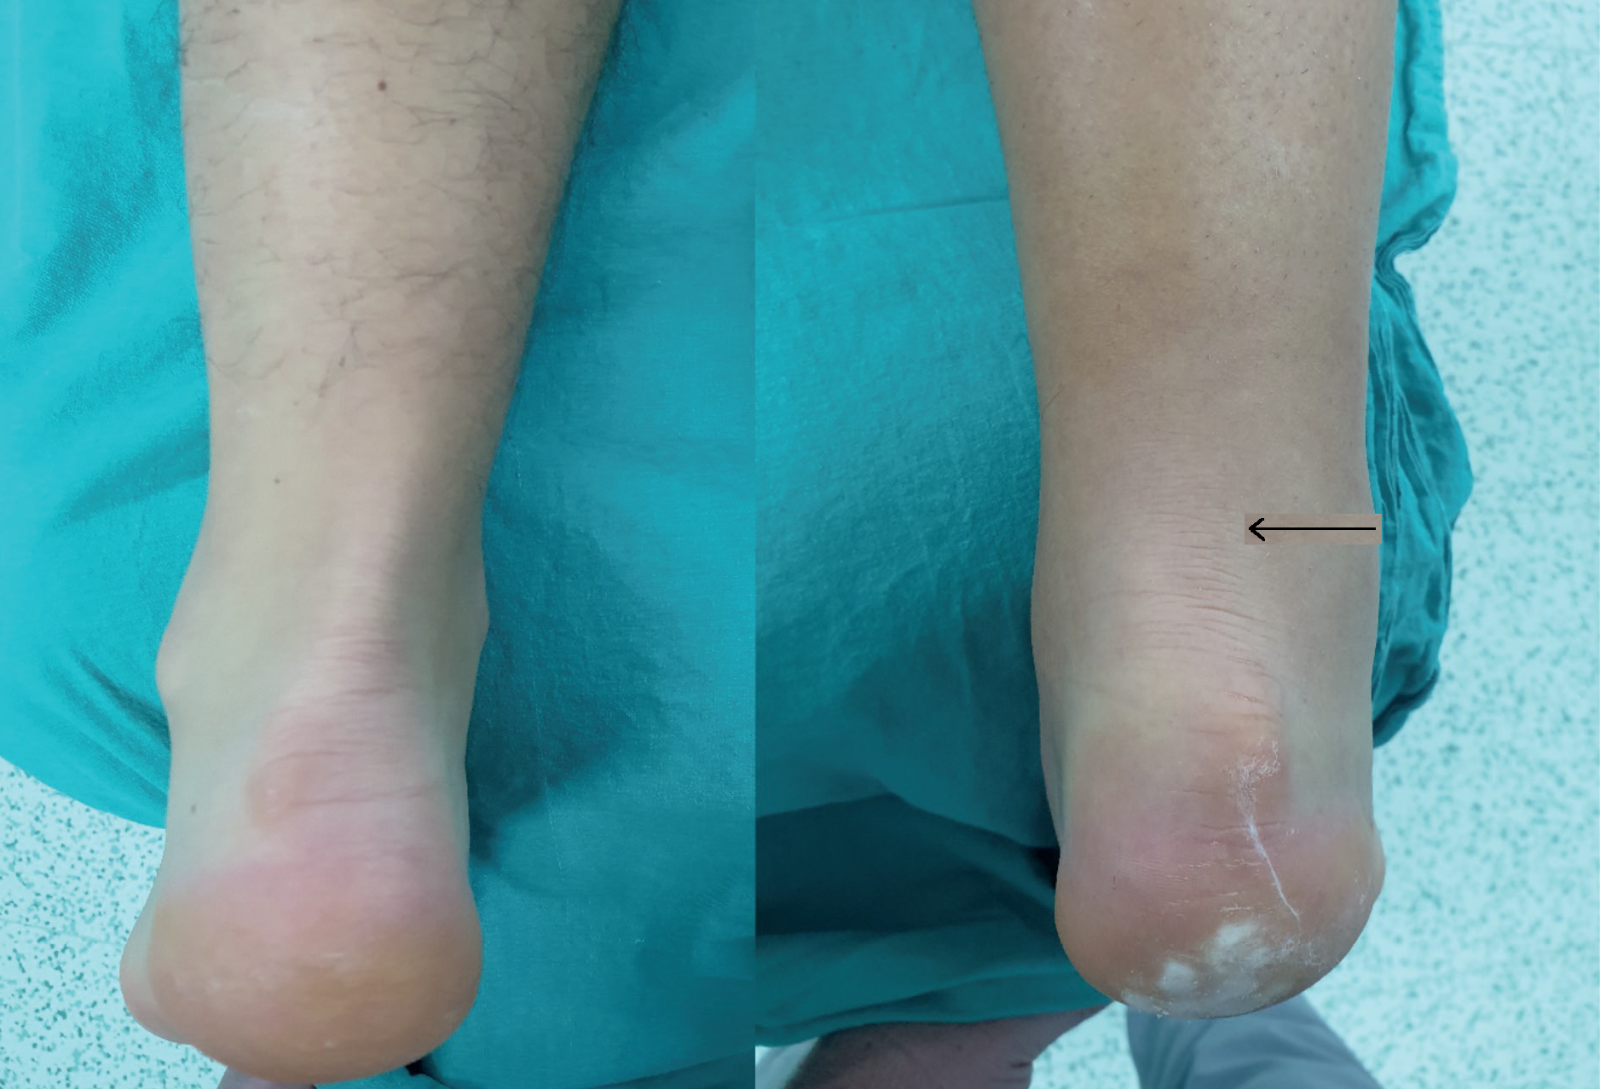

Sağ aşil tendon kopması olan hasta, solda sağlam tarafta ciltte aşil tendonunun gerginliği izlenirken sağda bu görünüm kaybolmuştur.